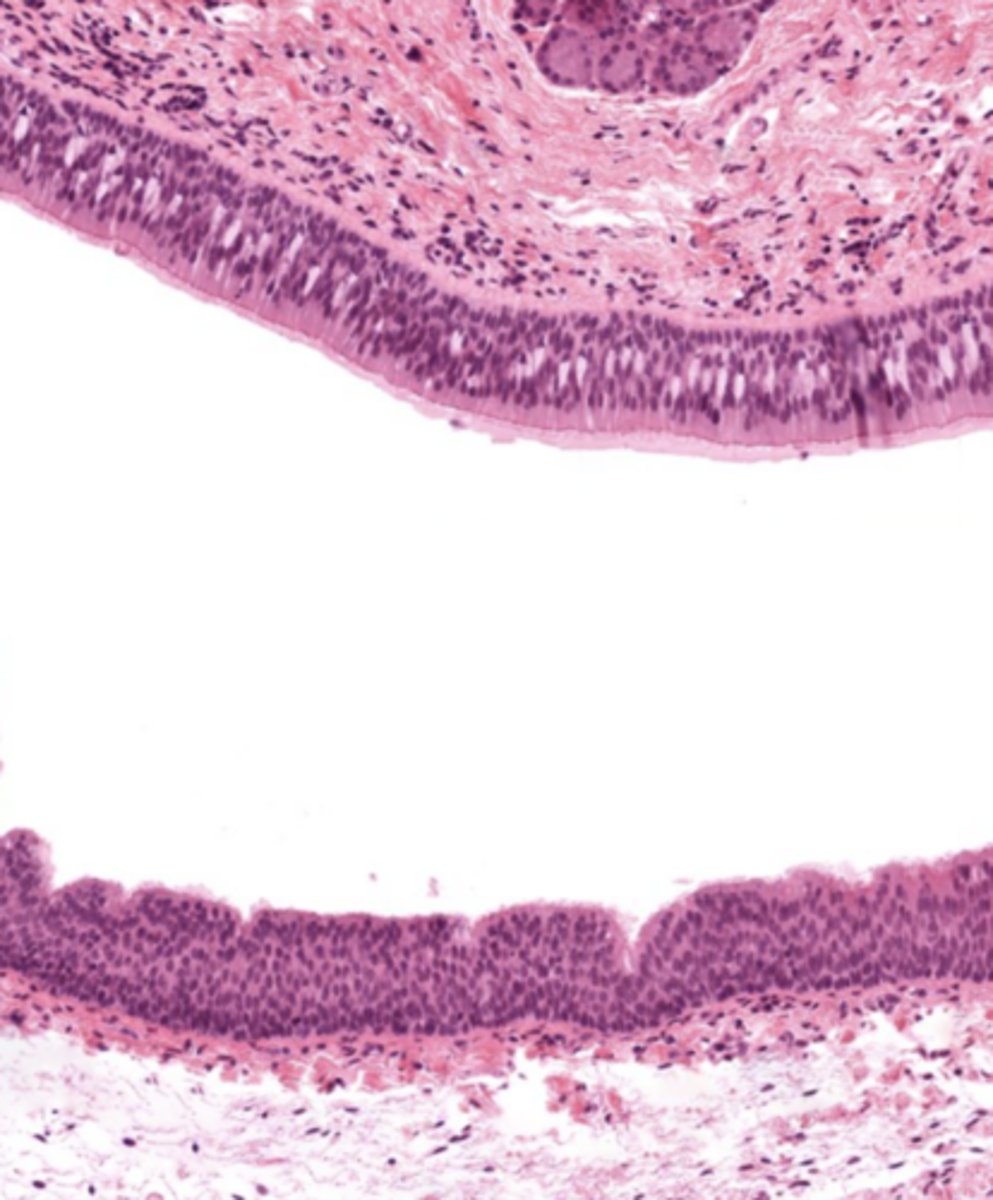

Pseudostratified ciliated epithelium -> stratified squamous epithelium (image is at the vestibular folds)

What epithelium covers vestibular folds?

Respiratory epithelium.

Understand how the epithelium changes from epiglottis to treachea`

Epiglottis - stratified squamous epithelium with elastic cartilage

False vocal cords - pseudostra. cillated epithelium

True vocal cords - stratified sq. non keratinized epithelium with skeletal muscle

Trachea - pseudostra. ciliated epithelium with goblet cells (respiratory structure)

False cords of the larynx

Identify the image

True cords of the larynx

Identify the image

Larynx (voice box)

Identify the entire structure

Describe the transitional epithelium of the larynx

The main transition occurs near the vocal cords, separating the squamous epithelium of the true vocal cords from the respiratory epithelium pseudostratified ciliated